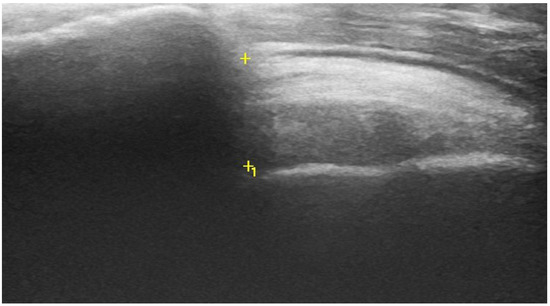

2.2. Acromiohumeral Distance (AHD)